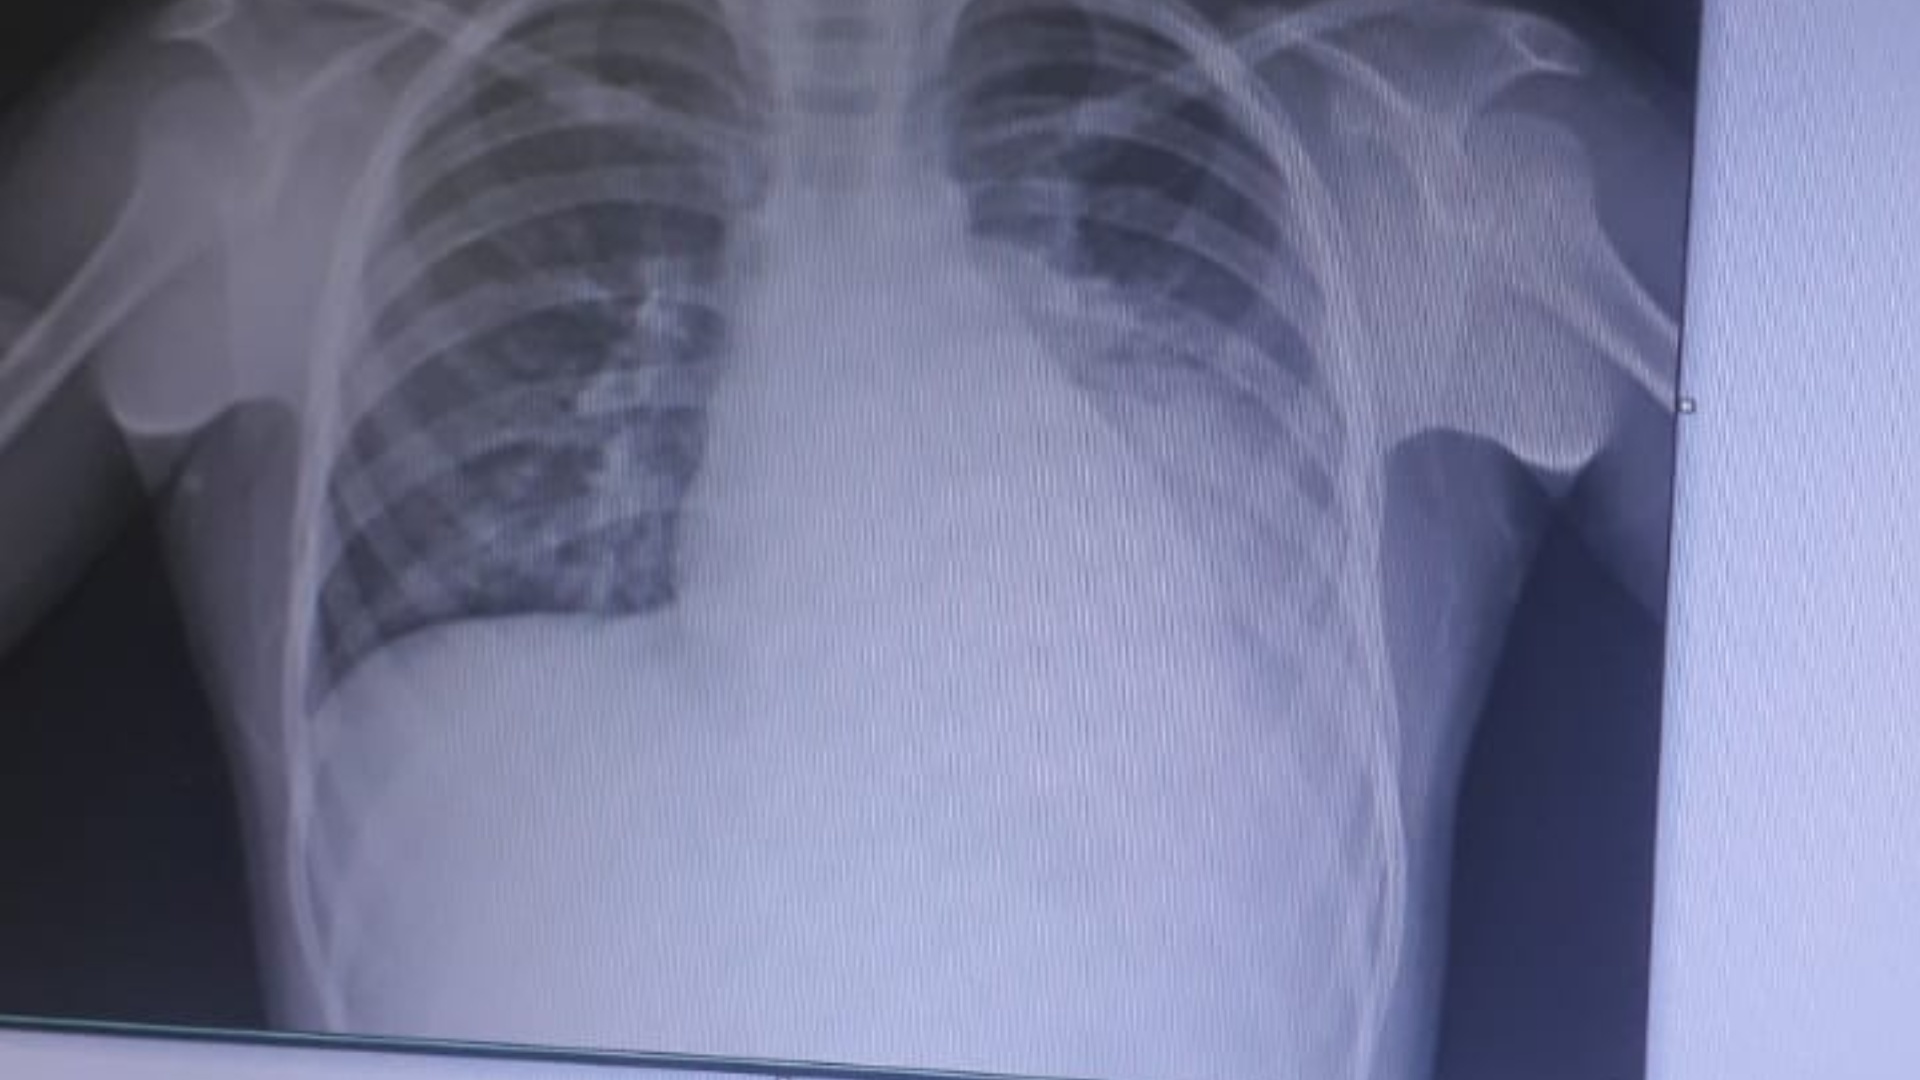

“Não fizeram nenhum raio-x nele. Eu pedi exame, pedi para receitar antibiótico, mas só passaram xarope pra ele”. O exame feito em hospital particular mostra que os pulmões estão comprometidos com uma pneumonia severa.

“O primeiro médico disse que seria virose, quando uma médica enviada por Deus viu ela [criança] reclamando de dores nas costas. O rosto estava inchado. O exame mostrou que ela estava com pneumonia e tinha tomado o pulmão esquerdo. Hoje ela está melhor, estamos no Hospital Regional, ela com um dreno no pulmão”.